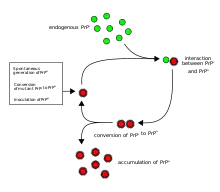

listen) is a misfolded protein that can transmit its misfolded shape onto normal variants of the same protein and trigger cellular death. Prions are the causative agent of prion diseases known as transmissible spongiform encephalopathies (TSEs) that are transmissible, fatal neurodegenerative diseases in humans and other animals.[3][4] The proteins may misfold sporadically, due to genetic mutations, or by exposure to an already misfolded protein.[5] The consequent abnormal three-dimensional structure confers on them the ability to cause misfolding of other proteins.

The first hypothesis that tried to explain how prions replicate in a protein-only manner was the heterodimer model.[52] This model assumed that a single PrPSc molecule binds to a single PrPC molecule and catalyzes its conversion into PrPSc. The two PrPSc molecules then come apart and can go on to convert more PrPC. However, a model of prion replication must explain both how prions propagate, and why their spontaneous appearance is so rare. Manfred Eigen showed that the heterodimer model requires PrPSc to be an extraordinarily effective catalyst, increasing the rate of the conversion reaction by a factor of around 1015.[53] This problem does not arise if PrPSc exists only in aggregated forms such as amyloid, where cooperativity may act as a barrier to spontaneous conversion. What is more, despite considerable effort, infectious monomeric PrPSc has never been isolated.

An alternative model assumes that PrPSc exists only as fibrils, and that fibril ends bind PrPC and convert it into PrPSc. If this were all, then the quantity of prions would increase linearly, forming ever longer fibrils. But exponential growth of both PrPSc and of the quantity of infectious particles is observed during prion disease.[54][55][56] This can be explained by taking into account fibril breakage.[57] A mathematical solution for the exponential growth rate resulting from the combination of fibril growth and fibril breakage has been found.[58] The exponential growth rate depends largely on the square root of the PrPC concentration.[58] The incubation period is determined by the exponential growth rate, and in vivo data on prion diseases in transgenic mice match this prediction.[58] The same square root dependence is also seen in vitro in experiments with a variety of different amyloid proteins.[59]

Transmission

It has been recognized that prion diseases can arise in three different ways: acquired, familial, or sporadic.[79] It is often assumed that the diseased form directly interacts with the normal form to make it rearrange its structure. One idea, the "Protein X" hypothesis, is that an as-yet unidentified cellular protein (Protein X) enables the conversion of PrPC to PrPSc by bringing a molecule of each of the two together into a complex.[80]